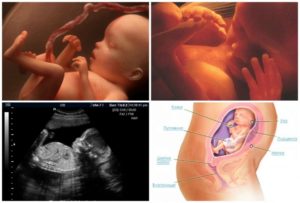

На 24 недели беременности плод весит около 600 г. Длина его достигает 28 см. В его развитии происходят следующие изменения:

- усиленно развивается мозг;

- развиваются моторика и вестибулярный аппарат;

- продолжают формироваться эпидермис и дерма;

- начинает вырабатываться гормон роста, который позволит плоду быстро набирать вес и активно расти;

- продолжает накапливаться подкожный жир;

- реснички и брови у плода становятся все более заметными;

- формирование органов и систем плода приходит к своему финишу.

Начиная с этой недели, происходит активное развитие головного мозга, формируются извилины и бороздки. В результате этого у плода усиливается работа органов чувств, проявляются новые рефлексы.

Центральная нервная система будущего ребенка также находится на стадии активного развития. Малыш может уже начинать приоткрывать глаза, они у него почти полностью сформированы. Уже генетически определён цвет его глаз.

Кожа все еще красная и сморщенная, но благодаря началу накопления особого подкожного бурого жира, вскоре она приобретет гладкость и ровность.

Важно! Ребенок на 24 неделе беременности энергично шевелится, свободно перемещаясь в околоплодных водах.

При этом период сна длится у него до 18 часов. На этом сроке ребенок уже хорошо различает звуки, поскольку органы слуха у него уже достаточно хорошо развиты. Еще он реагирует на свет, который просвечивается через живот мамы.Дыхательная система плода тоже сформирована, легкие начинают покрываться специальным веществом, которое будет препятствовать их пересыханию во время дыхания. Сейчас ребенок только тренируется дышать, получая кислород от матери, приходящий к нему с током крови.

Плод на 24 неделе беременности

Все самые основополагающие и важные формирующие процессы в развитии организма малыша по большей части закончились. Органы сформировались и теперь только «оттачивают» свою работу.

Задача малыша в ближайшие месяцы – набрать вес и окончательно подготовиться к появлению на свет:

- сейчас вес плода составляет около 450-500 г, а «рост» – 25-35 см (как виноградная гроздь или кукуруза);

- активно работают органы ЖКТ, печень, почки, селезенка;

- размеры сердца малыша уже позволяют рассмотреть его камеры и сосуды на УЗИ;

- формируются потовые железы;

- полностью сформировалось бронхиальное дерево;

- железы внутренней секреции плода начинают выработку веществ, активизирующих родовую деятельность женщины;

- совершенствуется мозг, углубляется рельеф коры головного мозга (извилины, борозды);

- движения малыша приобретают направленность, он учится их контролировать;

- большую часть времени малыш спит, накапливая силы и набирая вес.

У малыша понемногу начинает формироваться свой режим, который не всегда совпадает с периодами сна и бодрствования мамы.

Медики утверждают, что уже сейчас малыши в животе у мамы способны видеть сны. Поэтому не забывайте разговаривать с ребеночком и желать ему сладких снов.